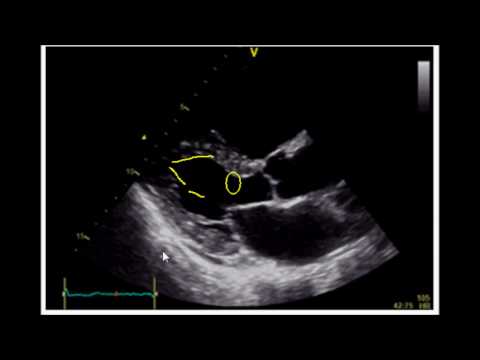

Making sense of your echo report